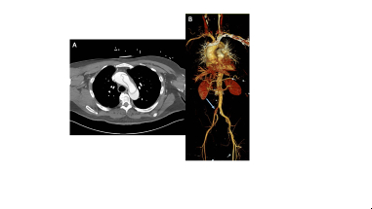

Five hours after presentation, he underwent emergent ascending aortic replacement, deep hypothermic circulatory arrest, and retrograde cerebral perfusion. The dissection flap originated at an anomalous right coronary artery (RCA) arising just above the commissure of the right and left coronary cusps. The proximal aortic wall (adventitia) was extremely thin (Fig 2), and the intimal flap was visibly mobile. Severe aortic insufficiency was addressed with aortic valve repair. Right lower extremity pulse returned with restoration of true lumen flow. Fasciotomy was also performed.